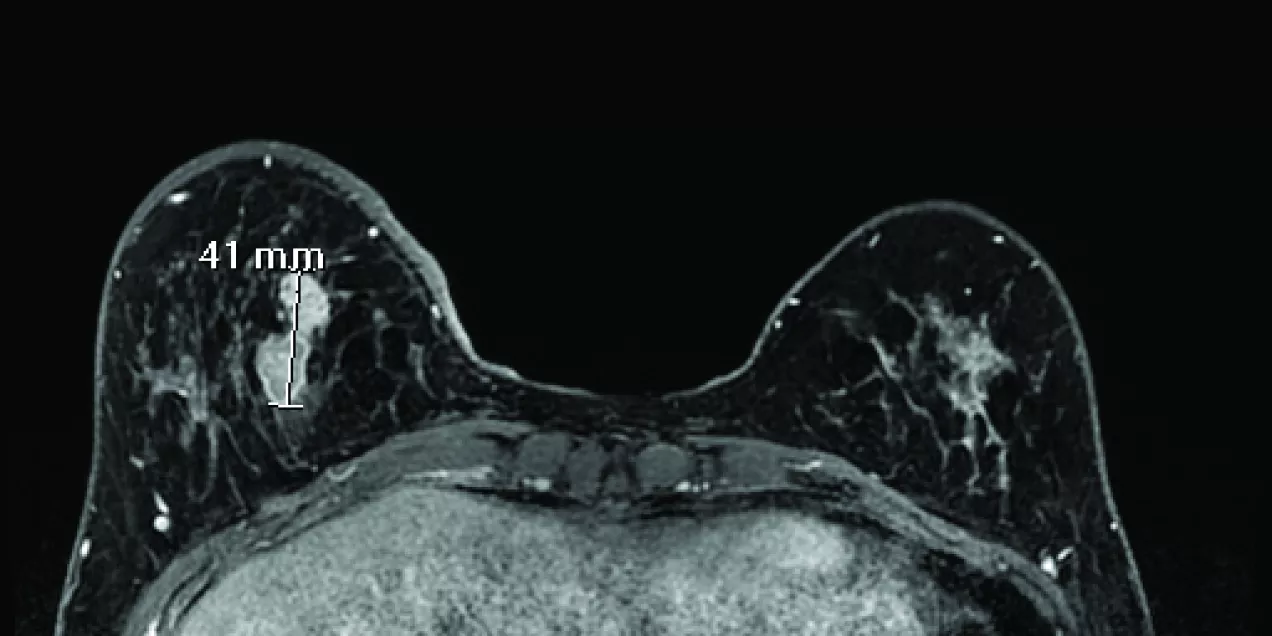

breast MRI scan showing both breasts in axial view with a bright enhancing lesion on the left side marked with a 41 mm measurement indicator, surrounded by fibroglandular tissue against a dark background

BI-RADS and Breast MR: How Well Are We Managing Patients Based on Established Standards?

While BI-RADS was initially used for communication in mammography, in 2003 the system was adapted to use with breast MRI, as the use of MRI for breast cancer detection and characterization has increased dramatically over the past decade.  The breast MR categories were most recently updated in 2013.